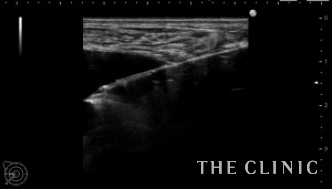

エコーでは右に6cmを超えるしこり(オイルシスト)、左にも3.5㎝のしこり(混合性のしこり)、小さなオイルシストも認めました。

右;オイルシストですがわずかに充実性成分も認めます。